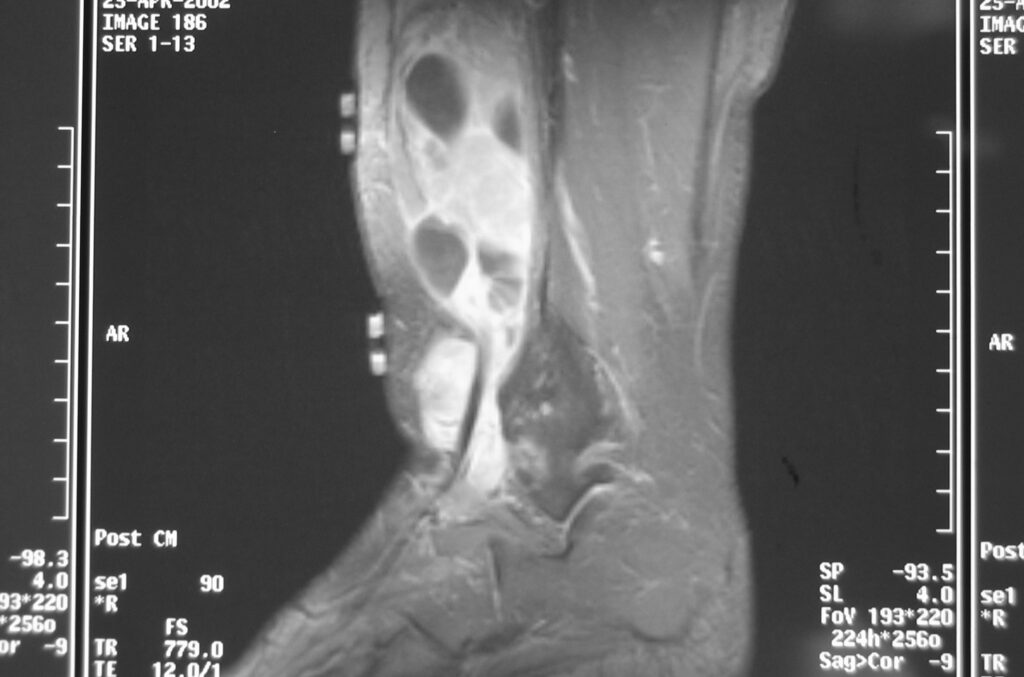

MRI

Shows multiloculated, heterogeneous mass.

“Triple Signal Intensity sign”; hypointense, isointense and hyperintense with fat on T2 – weighted MRI imaging. This sign is present in 30 to 50% of the cases. (Fig.3)

Under contrast enhancement Synovial Sarcoma appears heterogeneous and demonstrate areas of nodular enhancement.

In approximately 30% of cases a multiple vascular cannel may be identified

Synovial sarcomas may have a cystic appearance and are often mistaken for ganglion cysts especially those adjacent to tendons and in the foot and ankle.